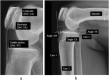

The positional relationship between patellar and femoral articular surfaces may vary according to the degree of posterior rotation of the tibial condyle, which may influence the patellar configuration. We hypothesized that the configuration of the patella has a rhomboid transformation similar to that of the tibial condyle. This cohort study included 313 patients with knee pain who underwent lateral-view knee digital radiography. The length of the long axis, short axis of the patella, and patellar tendon length of the patellofemoral joint were measured. The patella axis ratio (length of long/short axis) as patellar configuration and Insall-Salvati ratio were calculated. Correlations between the configuration of the tibial condyle and the three length parameters and the Insall-Salvati ratio were assessed. Posterior rotation and the rhomboid transformation of the tibial condyle were positively correlated with the length of the long axis of the patella and negatively correlated with the Insall-Salvati ratio. The more the tibial articular surface shifted posteriorly due to posterior rotation and rhomboid transformation of the tibial condyle, the longer the long axis of the patella was, and the smaller the Insall-Salvati ratio was. The long axis of the patella became longer due to rhomboid transformation, similar to the tibial condyle.